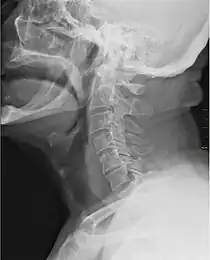

X-ray showing the throat, seen as a dark band to the front of the spine

In vertebrate anatomy, the throat is the front part of the neck, internally positioned in front of the vertebrae. It contains the pharynx and larynx. An important section of it is the epiglottis, separating the esophagus from the trachea (windpipe), preventing food and drinks being inhaled into the lungs. The throat contains various blood vessels, pharyngeal muscles, the nasopharyngeal tonsil, the tonsils, the palatine uvula, the trachea, the esophagus, and the vocal cords.[1][2] Mammal throats consist of two bones, the hyoid bone and the clavicle. The "throat" is sometimes thought to be synonymous for the fauces.[3]